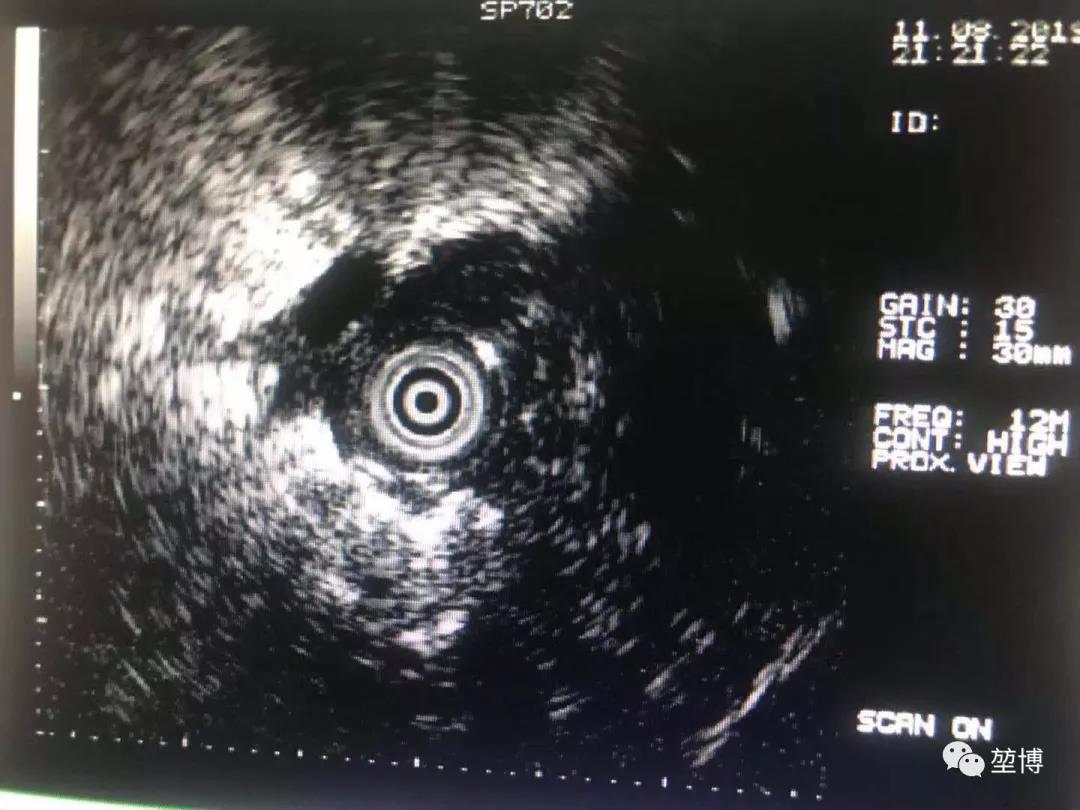

超声确认抵达病灶